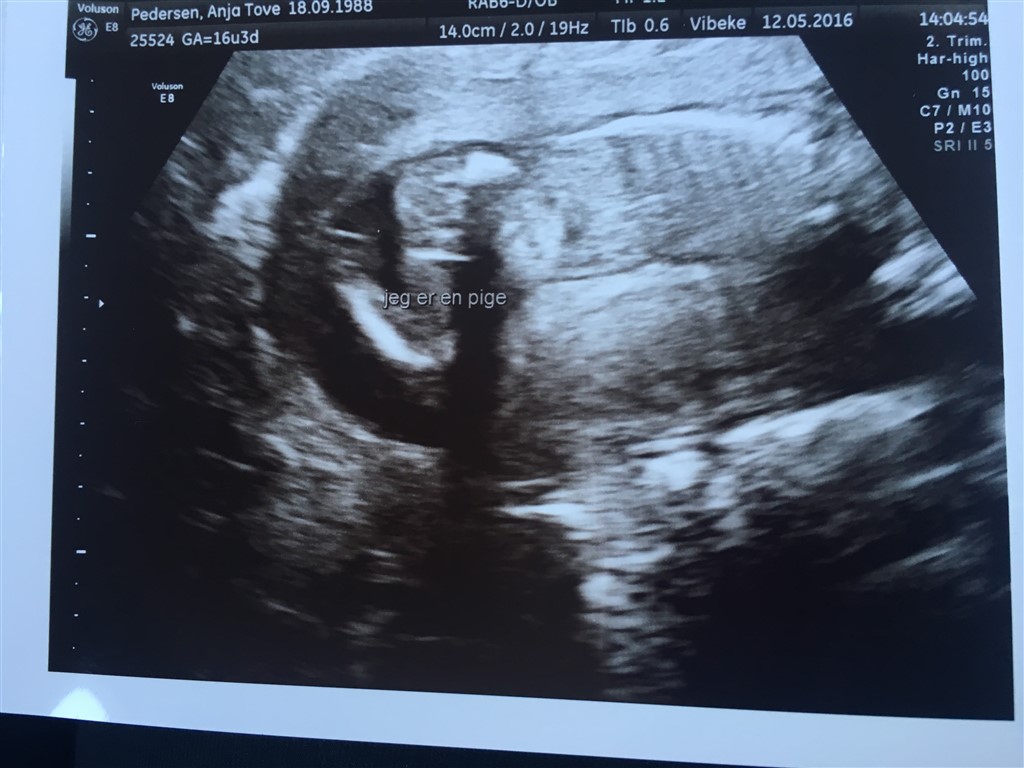

Vil starte med at sige at alt er som det skal være med babyen..

Næstved kunne ikke se kønnet, men babyen er præcis som den skal være. Flot vægt og flot længde. Hjerte, hjerne, lårben alt er lige præcis efter skalaen. Den danser rundt derinde. I forhold til Isaac er der meget meget mere liv denne gang.

Nå men blev da lidt skuffet over at hun ikke kunne se kønnet, men baby puttede med benene op under numsen så hun kunne slet ikke komme til.

Nu er jeg så blevet scannet igen og....

PRINSESSE

Billederne blev knap så gode, for hun er altså en putterøv

Vedhæftede fotos (klik for at se i fuld størrelse)